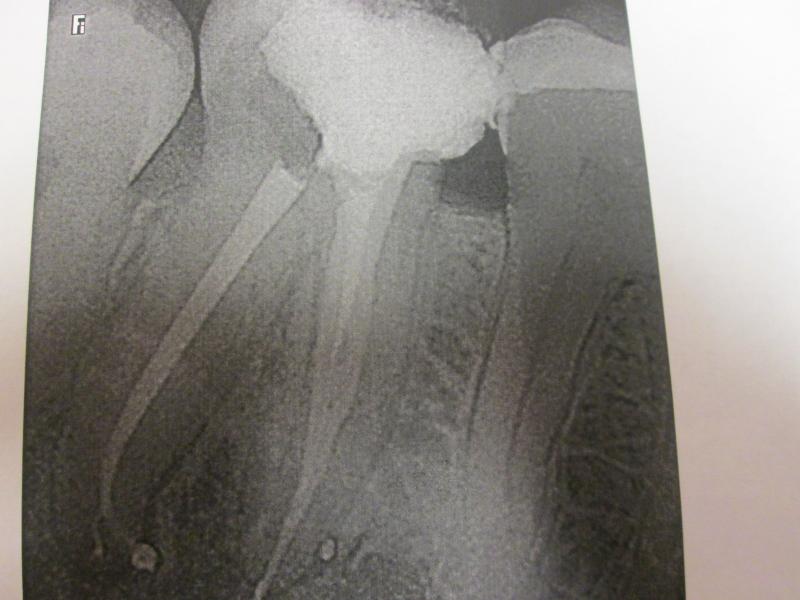

DR JET LOVES ROOT CANALS

"DR. JET'S MISSION IS TO PERFORM  ROOT CANALS FOR A REDUCED FEE USING THE LATEST TECHNOLOGY  AND TECHNIQUES TO SERVICE THE MANY PEOPLE WHO ARE UNINSURED OR UNDER-INSURED GIVING EVERYONE AN OPPORTUNITY TO SAVE THEIR TOOTH!"

ROOT CANALS by DR. JET (Jetepon Chiranand DDS)